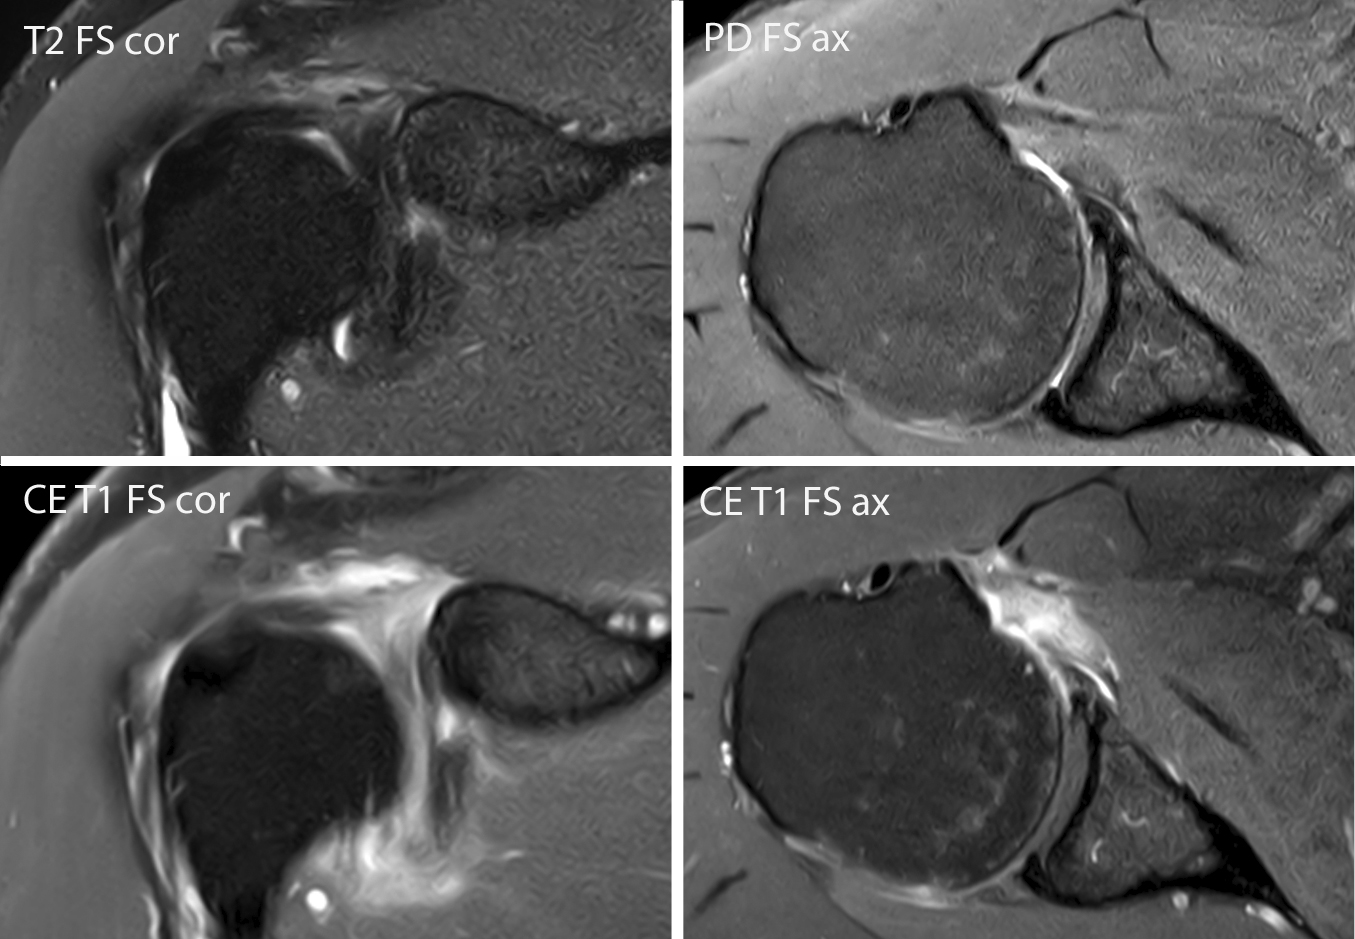

MRIESSENTIALS on Twitter "Adhesive capsulitis of the shoulder enhancement of the rotator Adhesive Capsulitis Rotator Interval Specific signs of adhesive capsulitis on ultrasound evaluation include thickening of the inferior recess of the glenohumeral joint. Using mri, axillary recess thickening, joint volume reduction, rotator cuff interval thickening, and proliferative. The rotator interval contains the chl, biceps tendon and the glenohumeral capsule. A contracted chl is considered the essential. The essential lesion is the tightened coracohumeral ligament and. Adhesive Capsulitis Rotator Interval.